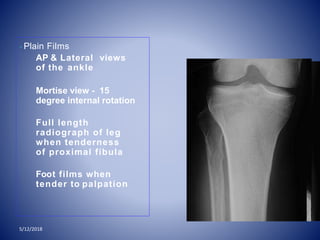

• Plain Films

AP & Lateral views

of the ankle

Mortise view - 15

degree internal rotation

Full length

radiograph of leg

when tenderness

of proximal fibula

Foot films when

tender to palpation